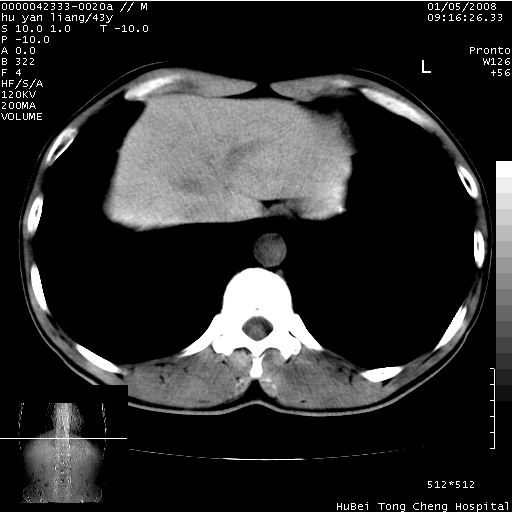

患者 男,43岁。右上腹不适1年余。既往有“肝右叶肝脓肿”病史,经保守治疗后痊愈。

b超提示:1)肝右叶肝内胆管结石。2)肝右叶占位性病变待排。

上中腹部ct轴位平扫+增强扫描(层厚10mm,螺距1.0,重建间隔10mm),图像如下:

肝右上叶偏后方较大团片状钙化灶,支持:肝脓肿后遗改变!

肝右叶后段团块状钙化灶,结合病史考虑肝脓肿痊愈后表现。